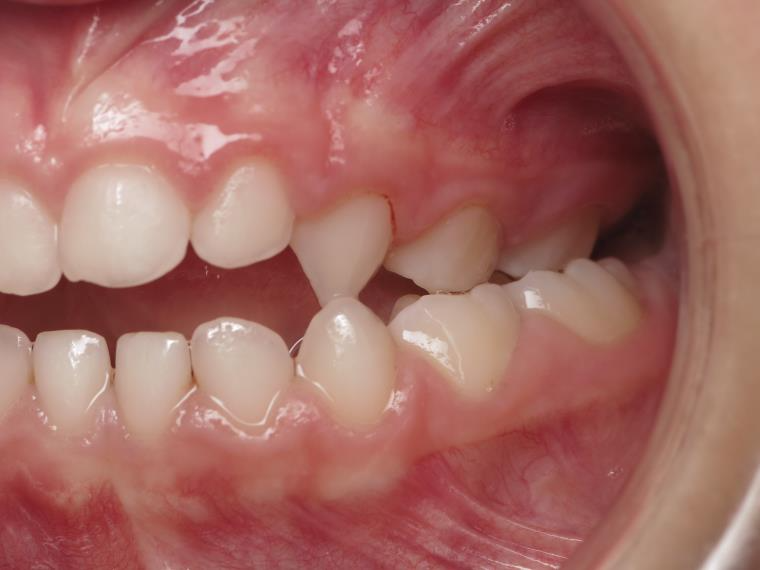

14 béance inversé gauche 5 ans

inversion postérieur coté droit et espace entre l'arcade du haut et du bas (béance)